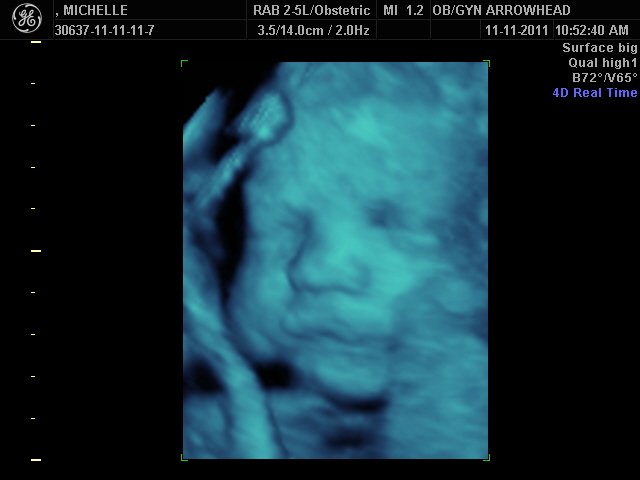

We offer complimentary 3D/4D Ultrasounds to all our OB patients around 30 weeks! The following photos are some examples of our work, shown with permission from our patients.